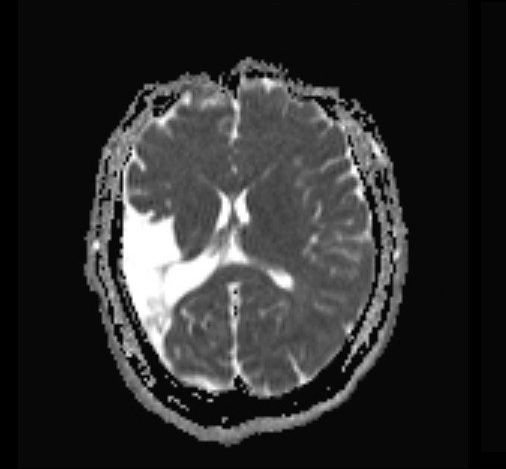

“A landmark report from the World Health Organization (WHO) has revealed that more than one in three people worldwide — over 3 billion individuals — are living with a neurological condition, making these disorders the leading cause of illness and disability across the globe.”